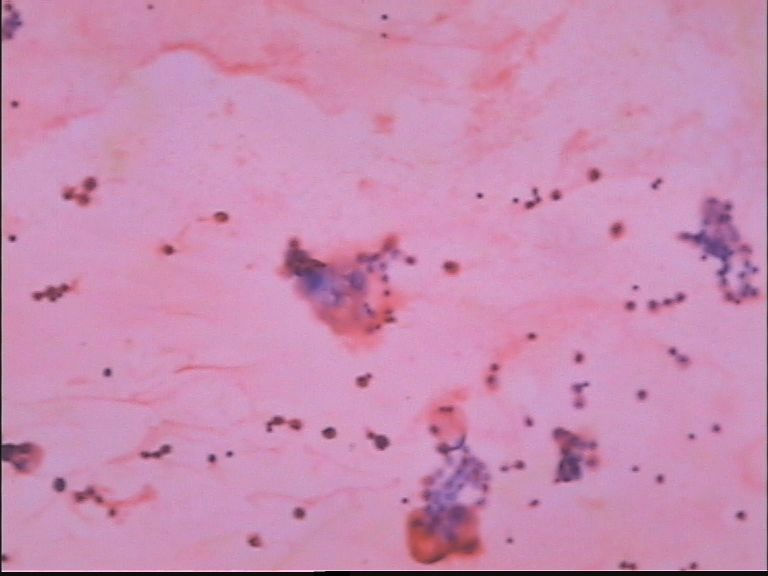

胸水 男67岁